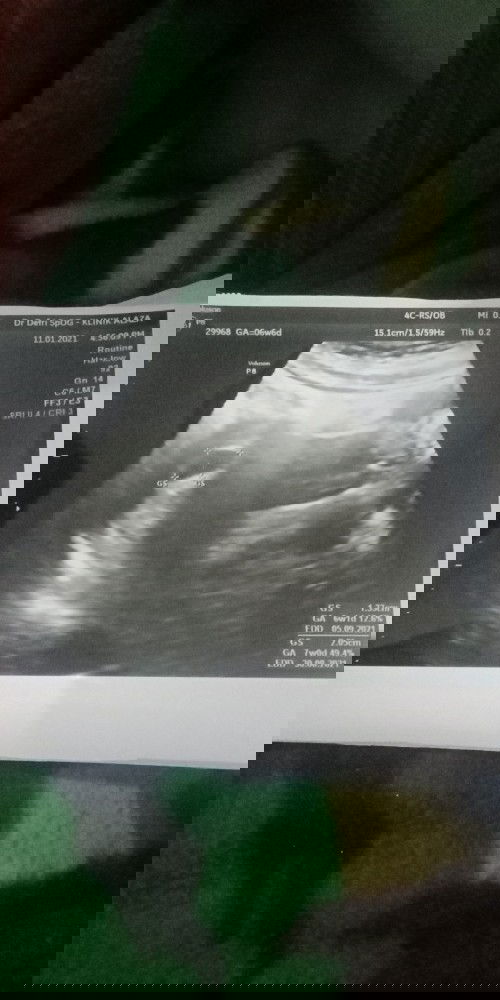

Hamil 6w6d masih terlihat kantong janin

Bun kemaren aku nyeri perut kiri bawah hilang timbul, sorenya usg kata dokter usia kandungan 6w6d masih kantong, belum ada detak jantung janin, dsuruh kontrol 2 minggu lagi Apa uk 6w6d belum bisa dengar detak jantung yaa bun? Ada pengalam yang sama bun?